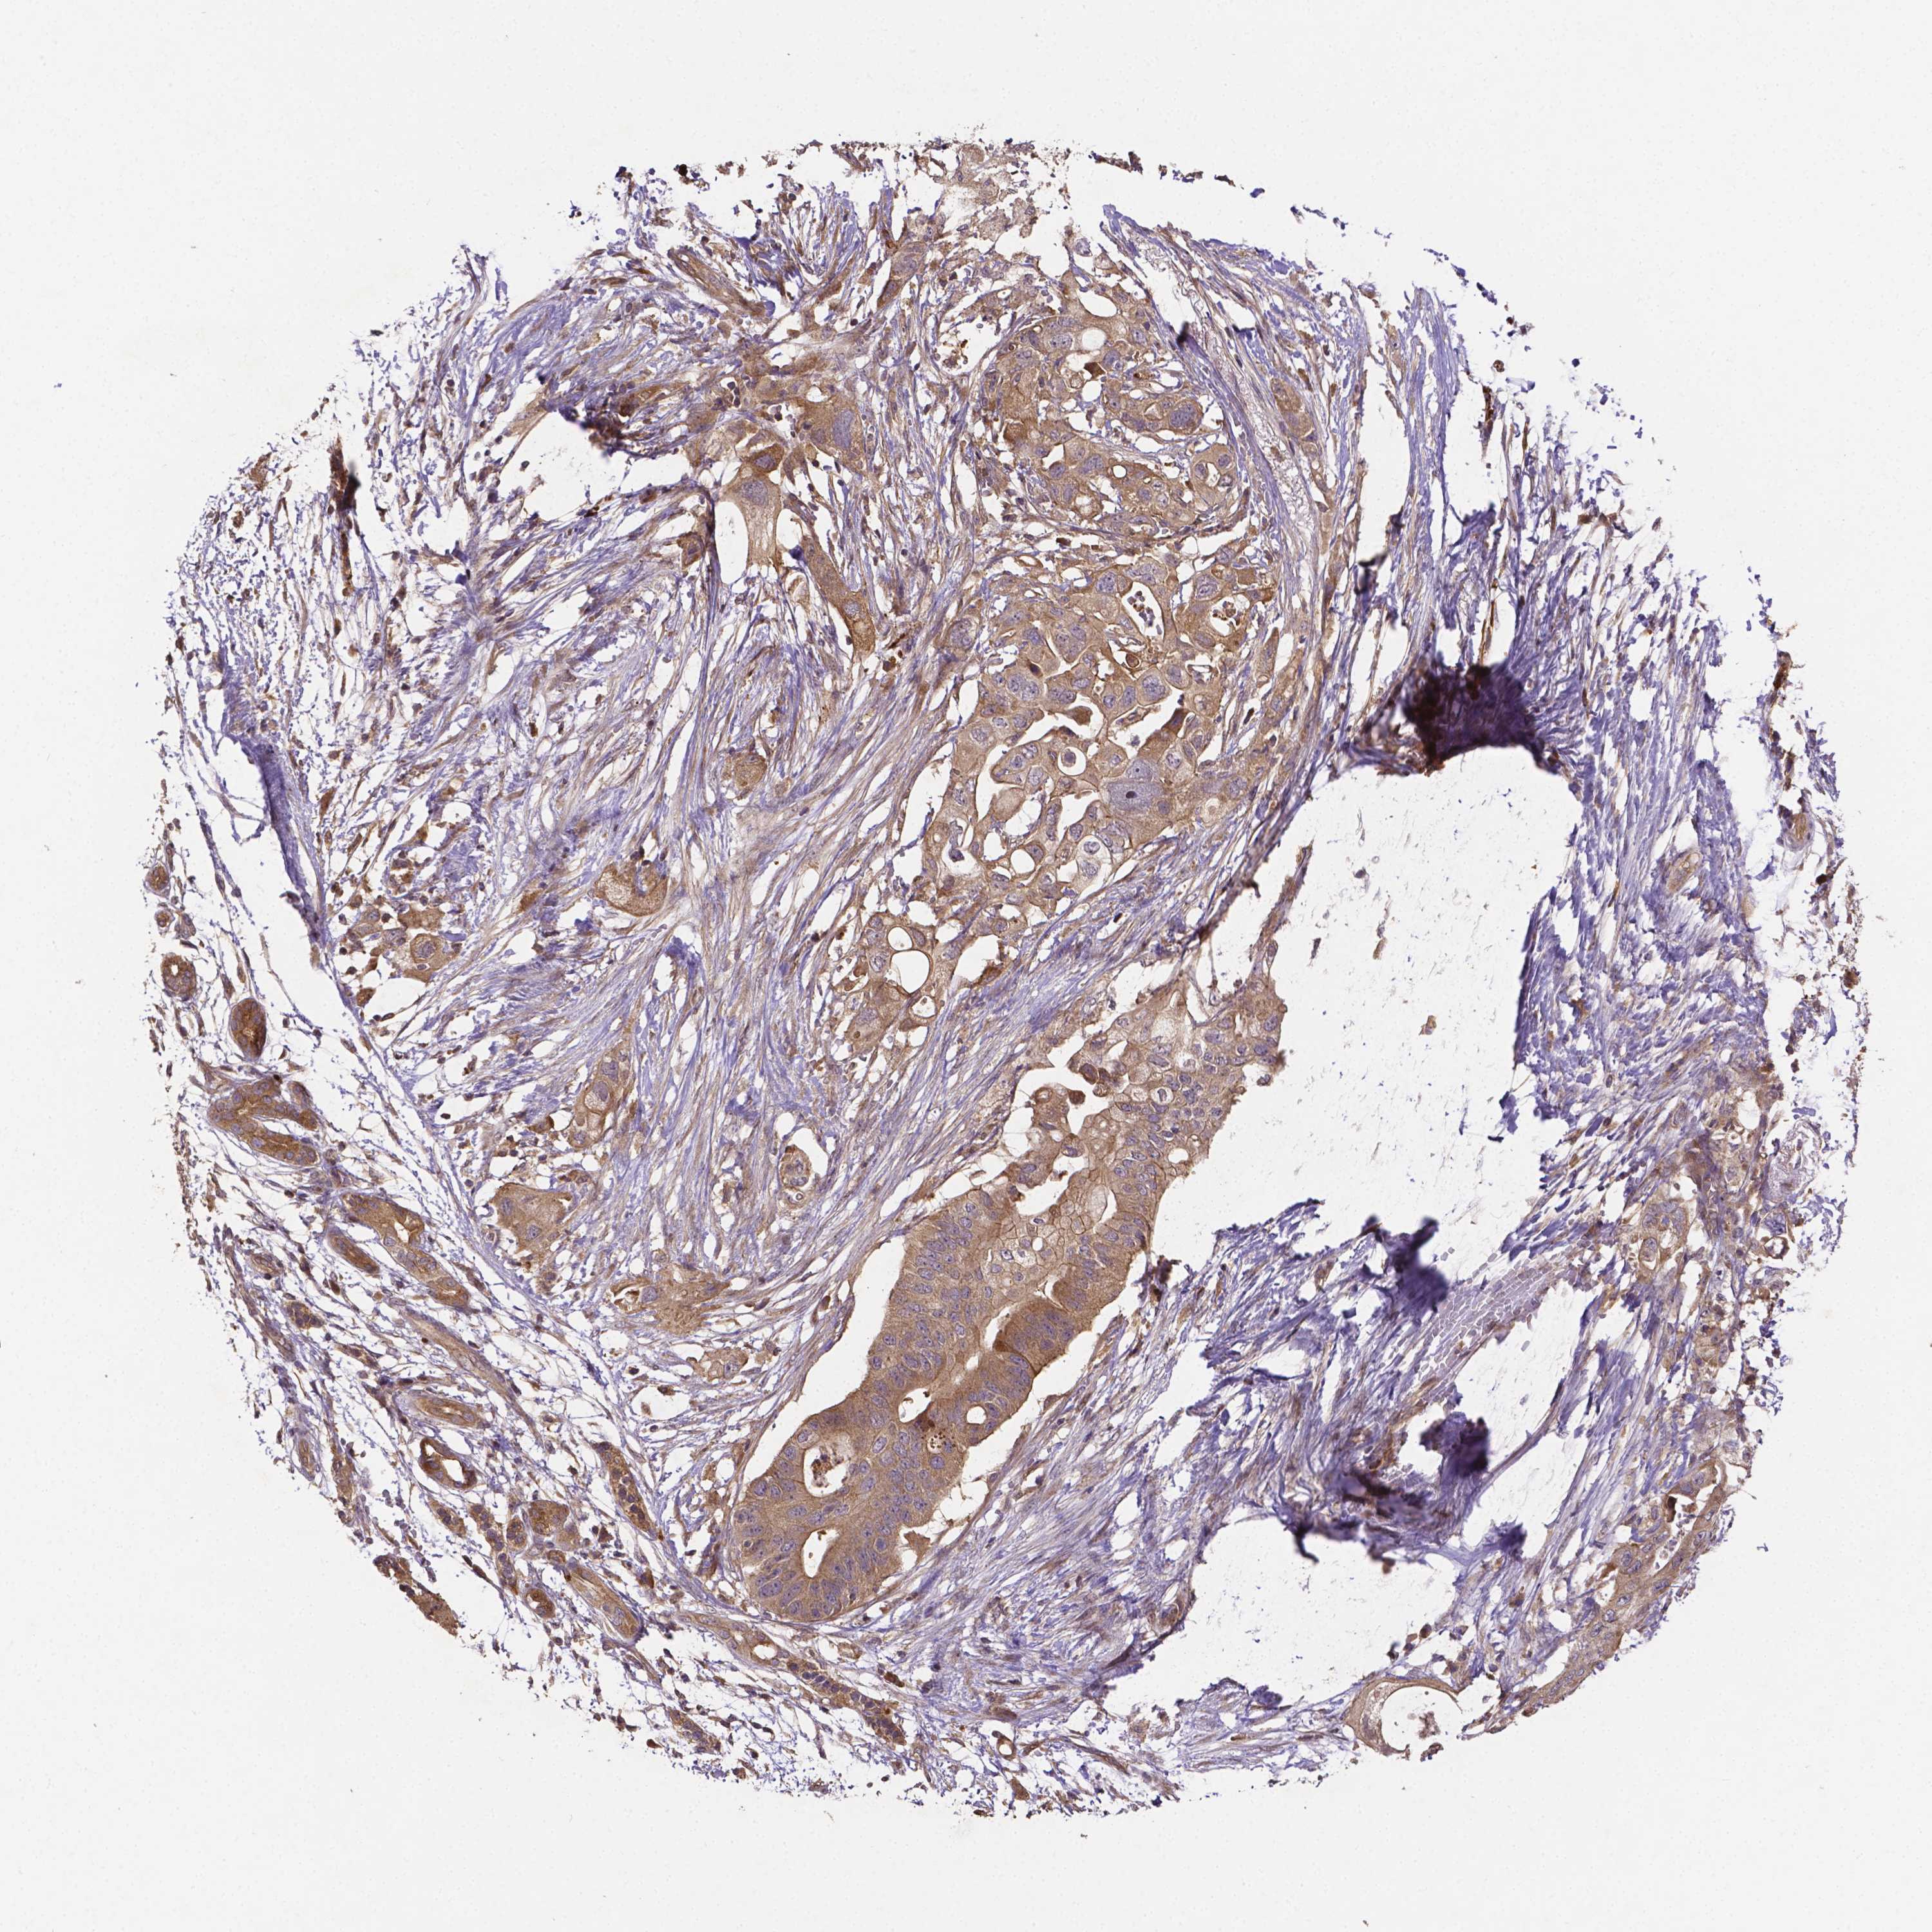

PANCREATIC CANCER - Protein expressioni

A mouse-over function shows sample information and annotation data. Click on an image to view it in a full screen mode. Samples can be filtered based on level of antibody staining by selecting one or several of the following categories: high, medium, low and not detected. The assay and annotation is described here.

Note that samples used for immunohistochemistry by the Human Protein Atlas do not correspond to samples in the TCGA dataset.

Antibody stainingi

Antibody staining in the annotated cell types in the current human tissue is reported as not detected, low, medium, or high, based on conventional immunohistochemistry profiling in selected tissues. This score is based on the combination of the staining intensity and fraction of stained cells.

Each image is clickable and will lead to virtual microscopy that enables deeper exploration of all samples and also displays staining intensity scores, fraction scores and subcellular localization as well as patient and tissue information for each sample.

Antibody HPA065983

Antibody HPA071879

Staining

High

Medium

Low

Not detected

Intensity

Strong

Moderate

Weak

Negative

Quantity

>75%

75%-25%

<25%

None

Location

Nuclear

Cytoplasmic/membranous

Cytoplasmic/membranous,nuclear

Adenocarcinoma, NOS